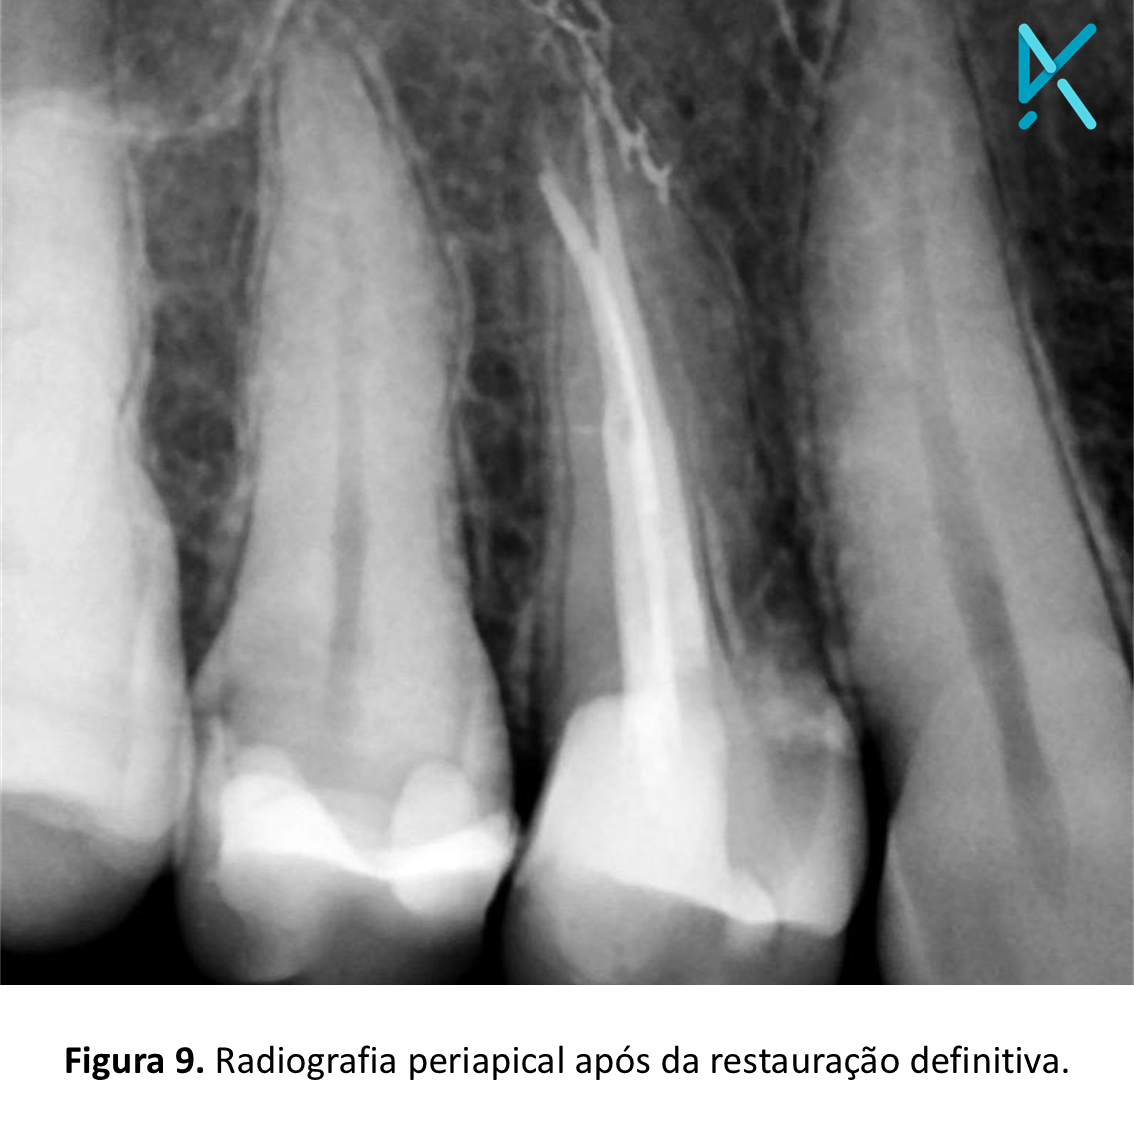

Após 4 minutos, constatada a presa do material, o conjunto de matriz e cunha foi removido. A escultura foi realizada com pontas diamantadas em forma de chama F e FF, e o acabamento e polimento, com o kit Twist-Gloss da American Burs. Posteriormente à remoção do isolamento absoluto, os contatos oclusais e os pontos de contato foram verificados.

A resina Stela apresenta grande versatilidade em casos de endodontia, por sua facilidade de aplicação, permitindo que, com rapidez e segurança, o profissional entregue a blindagem e a restauração definitiva da cavidade em poucos minutos.